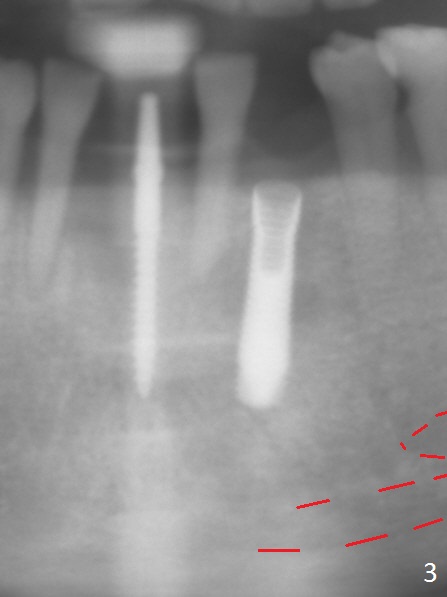

Before surgery, the patient reports that the tooth #25 has inclined to the position of #24 since the latter was extracted (Fig.1). After extraction of the tooth #25, there seems to be more bone vertically at the site of #24 than that of #25. Therefore the osteotomy is initiated at #24. The edentulous space is 9 mm mesiodistally, whereas the incisor width is 6 mm. The first pilot drill is fractured (1.2 mm). The latter is retrieved with incision. With better visibility, the initial osteotomy is found buccal. When a 3x14(2) mm dummy 1-piece implant is being placed partially, the buccal plate seems to be thin. A 2.5x14(4) mm 1-piece implant is placed instead with stability (Fig.2).